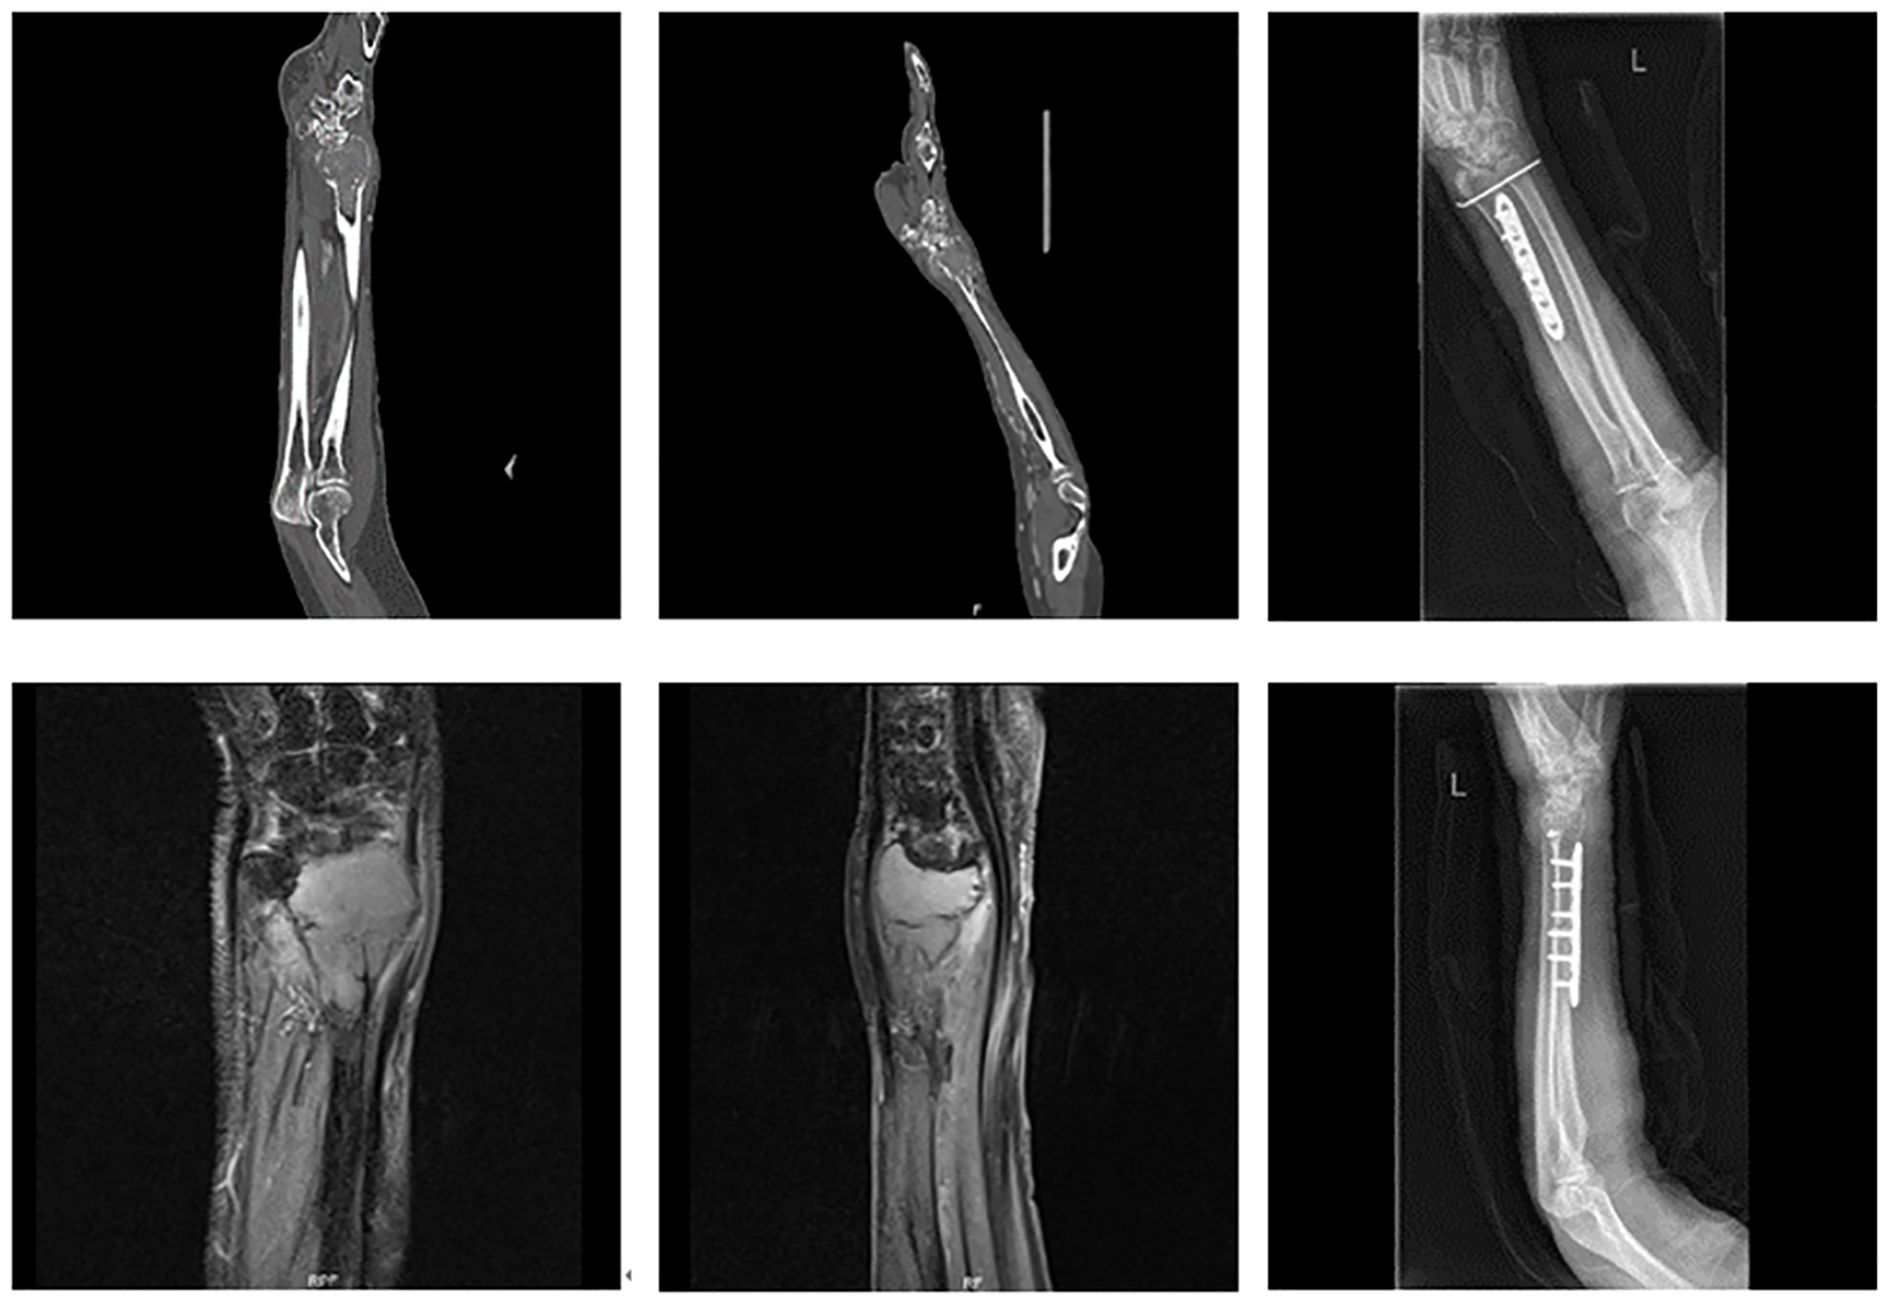

Tumors confined to the distal radius (Figure 1): Resection of the distal radius followed by joint-preserving reconstruction using either autologous fibular grafts or 3D-printed prostheses.

Figure 1. Tumor confined to the distal radius without involvement of the distal radioulnar joint or distal carpal bones.

Tumors involving the distal radius, proximal carpal bones, and/or distal ulna (Figure 2): Resection of the involved structures, followed by wrist arthrodesis using either autologous fibular grafts or ipsilateral ulnar transposition with arthrodesis.

Figure 2. Tumor involving the distal radius with extension to the distal carpal bones and/or the distal radioulnar joint: (A) involving only the distal carpal bones; (B) involving only the distal radioulnar joint; (C) involving both the distal carpal bones and the distal radioulnar joint.

Six cases involved isolated resection of the distal radius. Of these, five underwent joint-preserving reconstruction—four with autologous fibular grafts and one with a 3D-printed prosthesis (Figure 5). In one case, where tumor involvement exceeded 50% of the radial length, reconstruction was performed using ulnar-only fixation and ulnar-wrist arthrodesis (Figure 6).

Figure 5. A 69-year-old female with undifferentiated sarcoma of the left distal radius. The patient underwent large segmental resection and reconstruction with an autologous fibular graft.

Figure 6. A 74-year-old male with carcinosarcoma of the distal right radius involving more than half of the bone. The patient underwent large segmental resection followed by ulnar-wrist arthrodesis.